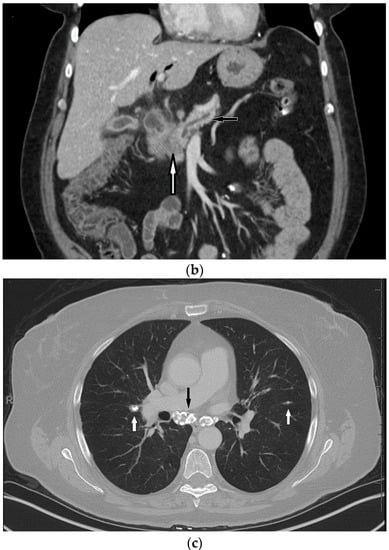

3. Case Presentation